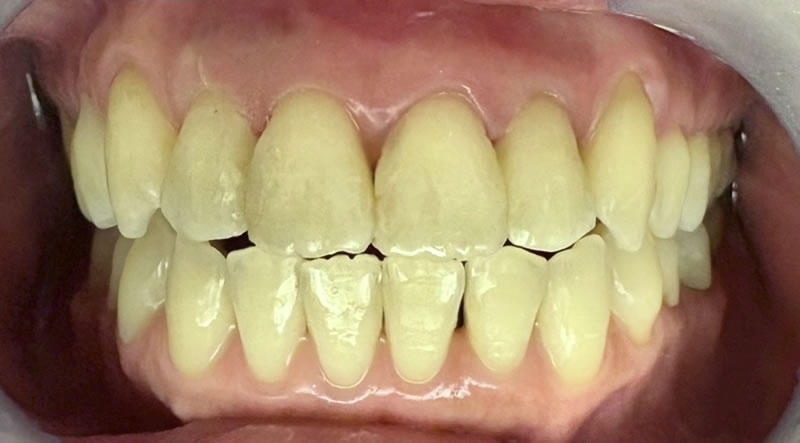

矯正後の60代後半女性で、下の前歯の歯茎下がりの空隙部位に食べものが入ってしまったり唾液が飛ぶから、封鎖したいという主訴でした。

ダイレクトボンディングによる歯の形態修正で足場を作り、ヒアルロン酸をキャリアにした幹細胞由来サイトカインとレーザーによる治癒促進治療による歯周組織再生誘導を同時に併用しました。